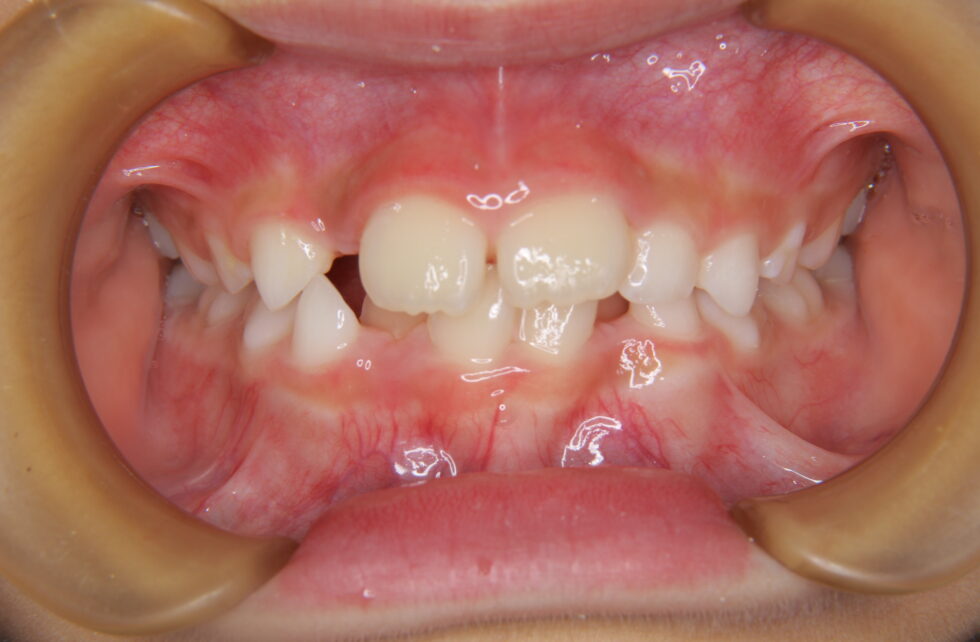

初診時年齢8歳の女子 下顎前歯部の叢生を主訴に来院された。

永久歯の配列余地が著しく不足していたが、上下顎の前後的なずれはなく中立咬合の叢生と診断した。Ⅰ期治療を7か月間(調整来院6回)行い、経過観察期間を経て13歳から上下顎マルチブラケット装置を使用して非抜歯でⅡ期治療を行った。Ⅱ期治療は来院間隔が長く2年6か月間を要したが、調整来院は14回であった。動的治療期間はⅠ期Ⅱ期合わせ3年1カ月間、調整来院は20回であった。